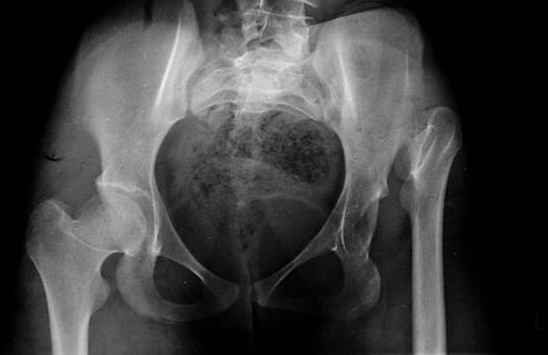

Devushka predstavlennaya na snimke nachala s LLD 9 cm, valgus deformation of the tibia, huge Trendelenburg( vidno na snimke).

Seichas : no LLD ,no Trendelenburg, reasonable hip motion.A samoe glavnoe ei ne predstoit kaghdye 10-15 let delat revision THR.